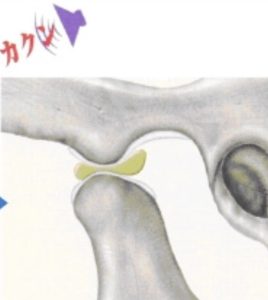

カクカクと音が鳴るわけ

関節円板が前方にズレていて、変形してる状態。

口を開けると、下顎頭が変形した関節円板に引っかかる。

引っ掛かりが外れて下顎頭がさらに前に出るときに、カックンと音が鳴る。